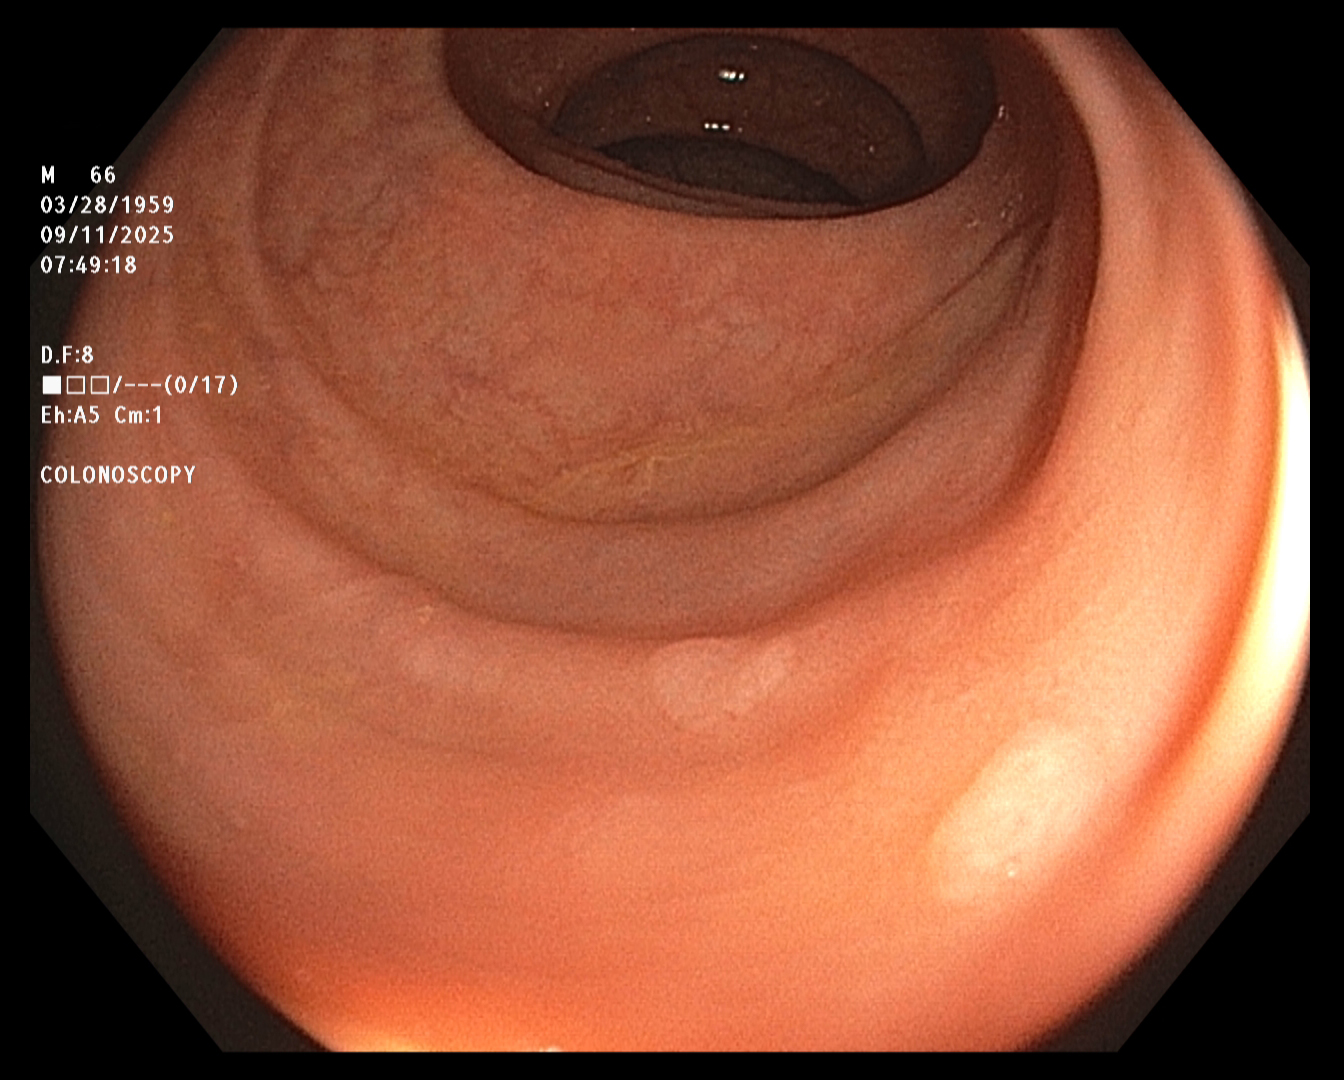

The endoscopist in this study generated a series of images showing the cecum and several sites

of concern (e.g., polyps). The cecum is the beginning of the colon, so reaching it ensures that

the entire colon will be examined. The endoscope was slowly withdrawn, while the endoscopist

assayed mucosal detail and identified and removed several polyps for later examination. The

first and last images were taken about twenty minutes apart.

Terminal Ileum